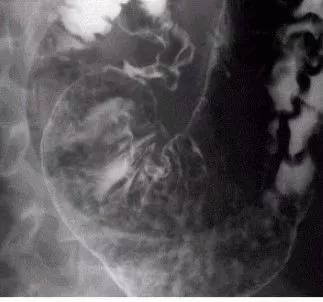

十二指肠球部溃疡X线影像

A 充盈相示:大弯侧腔外龛影;B 双对比相示:前后壁两个溃疡相吻